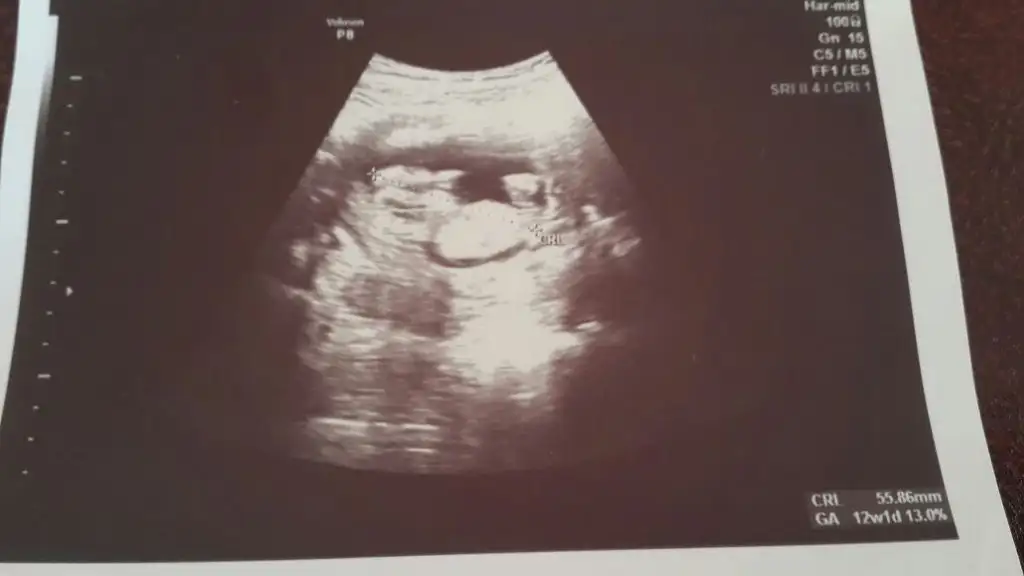

sanki umrumda bana yorum yapmışmıydın önceden buda benim 12 haftalık olan bebişim .bakarmısın benim içinde.

Canım kıza biraz daha fazla benziyor. Ama görüntü kalitesi çok iyi değil. Yanılma Payı ile kız diyorum :)